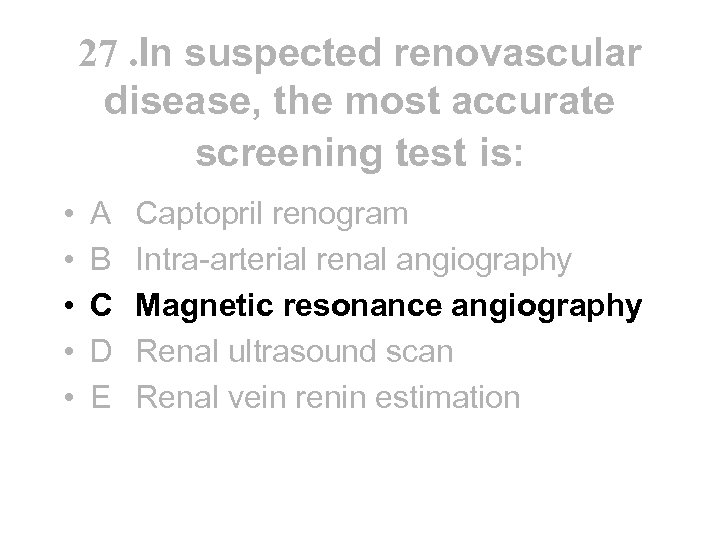

27 In suspected renovascular disease, the most accurate screening test is: • • • A B C D E Captopril renogram Intra-arterial renal angiography Magnetic resonance angiography Renal ultrasound scan Renal vein renin estimation

27 In suspected renovascular disease, the most accurate screening test is: • • • A B C D E Captopril renogram Intra-arterial renal angiography Magnetic resonance angiography Renal ultrasound scan Renal vein renin estimation

27. In suspected renovascular disease, the most accurate screening test is: • • • A B C D E Captopril renogram Intra-arterial renal angiography Magnetic resonance angiography Renal ultrasound scan Renal vein renin estimation

27. In suspected renovascular disease, the most accurate screening test is: • • • A B C D E Captopril renogram Intra-arterial renal angiography Magnetic resonance angiography Renal ultrasound scan Renal vein renin estimation

• • • Diagnosis - suspect in arteriopath with difficult HT or ACEI renal failure - renal sonar may show inequality of renal size (>1. 5 cms) - captopril renogram is ok screening test if renal function normal - MRA now considered best screening test - intra arterial renal angio is still the gold standard for diagnosis - renal vein renin ratio may predict response to revascularisation Treatment - control of HT avoiding ACEI/ARB if possible - aspirin and statin for their anti ischaemic effect - revascularisation by PTRA/stent if BRVD with >60% stenoses and pulmonary oedema, difficult HT or need to use ACEI/ARB • Outcome • - high mortality from extra renal vascular disease and don’t usually do well on dialysis

• • • Diagnosis - suspect in arteriopath with difficult HT or ACEI renal failure - renal sonar may show inequality of renal size (>1. 5 cms) - captopril renogram is ok screening test if renal function normal - MRA now considered best screening test - intra arterial renal angio is still the gold standard for diagnosis - renal vein renin ratio may predict response to revascularisation Treatment - control of HT avoiding ACEI/ARB if possible - aspirin and statin for their anti ischaemic effect - revascularisation by PTRA/stent if BRVD with >60% stenoses and pulmonary oedema, difficult HT or need to use ACEI/ARB • Outcome • - high mortality from extra renal vascular disease and don’t usually do well on dialysis